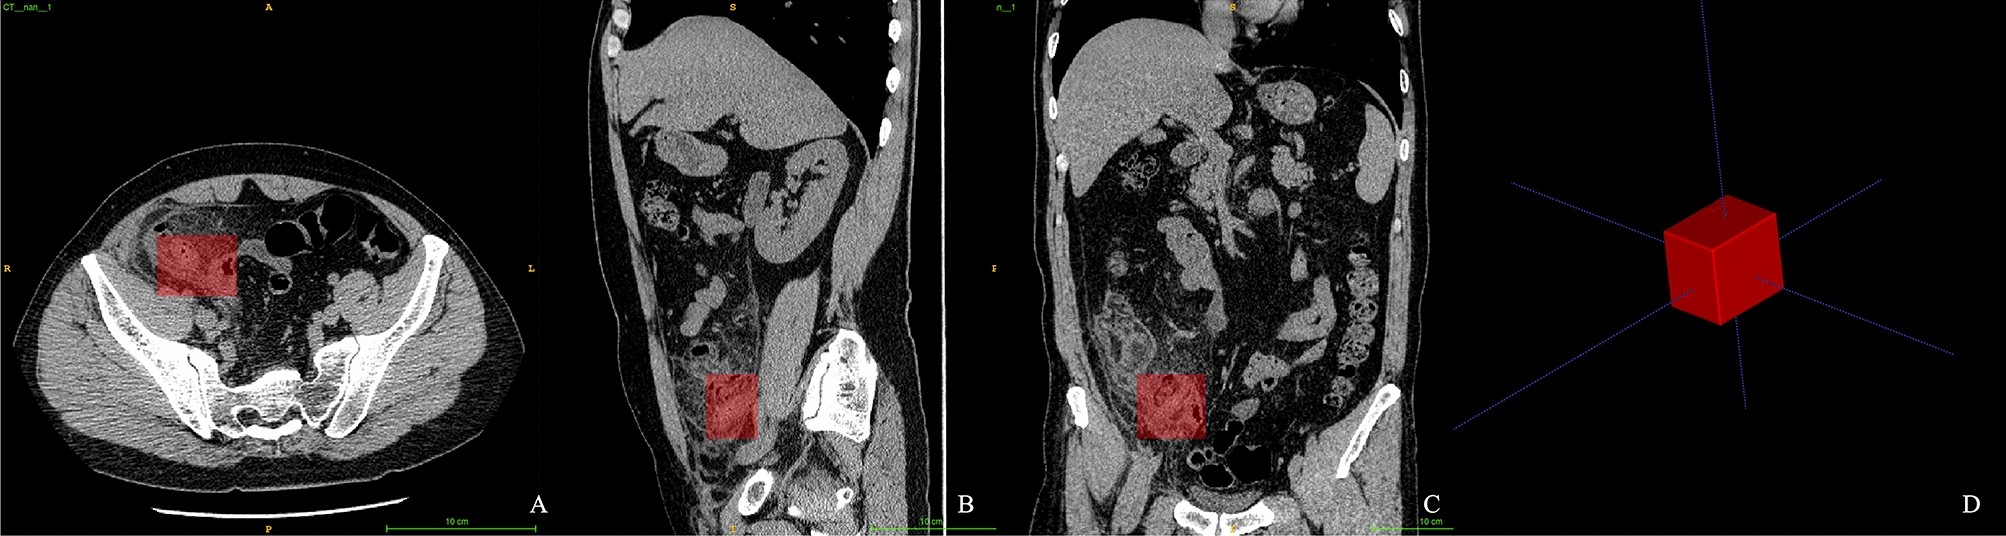

Figure 2

Region of interest of the models. A rectangle-shaped ROI was annotated, covering the areas of the end of the cecum and appendix. The ROI is shown in axial (A), sagittal (B), and coronal (C) planes and viewed three dimensionally (D).